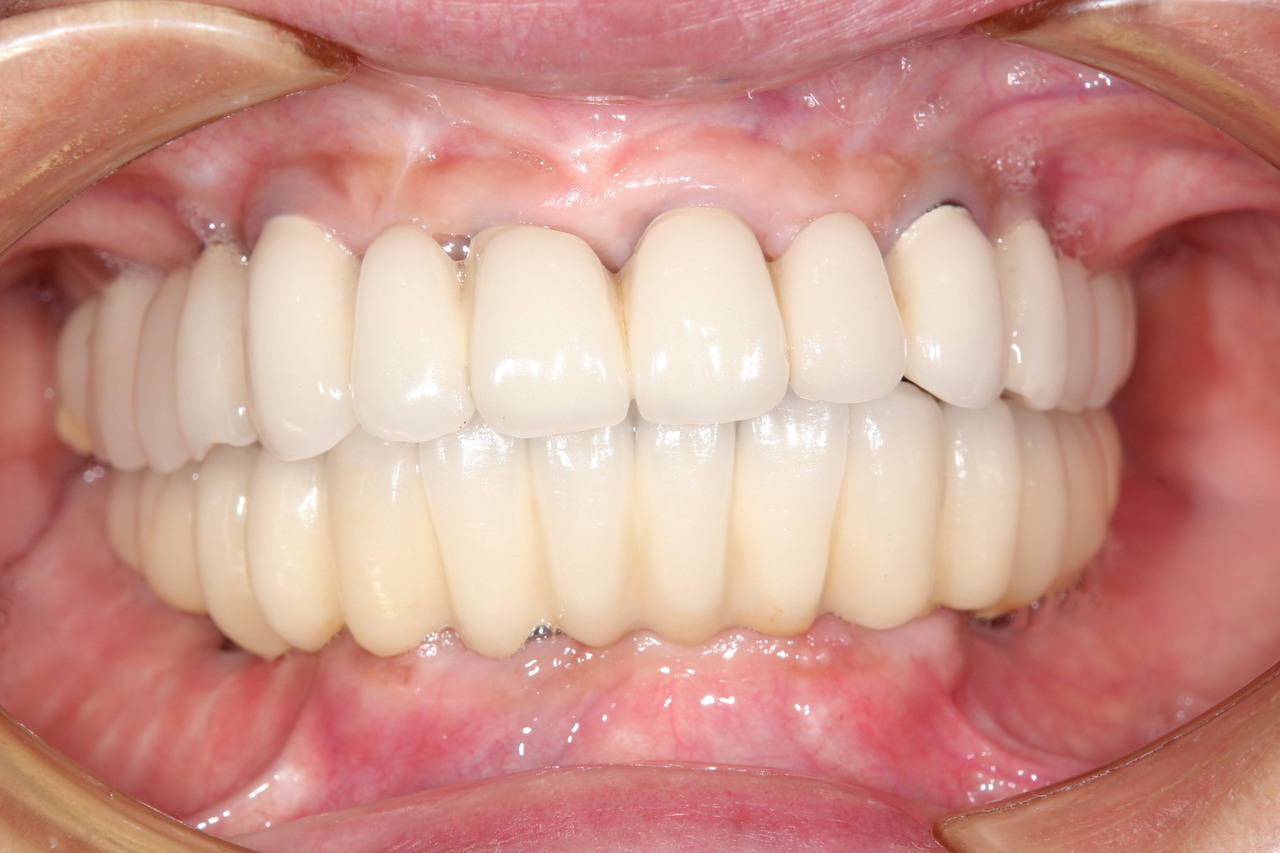

最終的な被せ物装着

インプラントがしっかり骨に定着したら、型取りをして、最終的な被せ物を製作し、装着します。

完成後のレントゲン写真

最終的な被せ物を装着した状態のレントゲン写真。

(今回は下顎ですが、その前に上顎は治療済みです。)